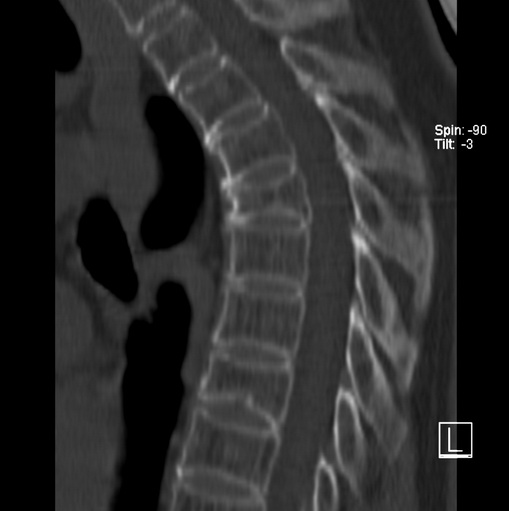

标题: CT25377:脊柱有无压缩骨折?

女、73、胸痛、胸闷3个月,无明显外伤病史,x线疑t4、t7陈旧压缩骨折,ct未经明显骨折,请问结论如何报?

老年女性病人,骨质稀疏,有些驼背,t4明显变扁,t7略变扁,椎体边缘无中断,骨小梁排列正常,无嵌插所致致密线。结合无明显外伤史,考虑老年骨质稀疏,慢性压缩改变,正如老年人骨质稀疏椎体呈双凹改变一样。我考虑报:老年骨质稀疏,t4、t7楔形变,脊柱曲度改变(驼背).敬请大家指教。

1)多个胸椎陈旧性压缩性骨折。2)胸椎普遍性骨质疏松。3)胸椎退行性改变。

1)多个胸椎陈旧性压缩性骨折[骨质疏松所致]。2)胸椎普遍性骨质疏松。3)胸椎退行性改变。